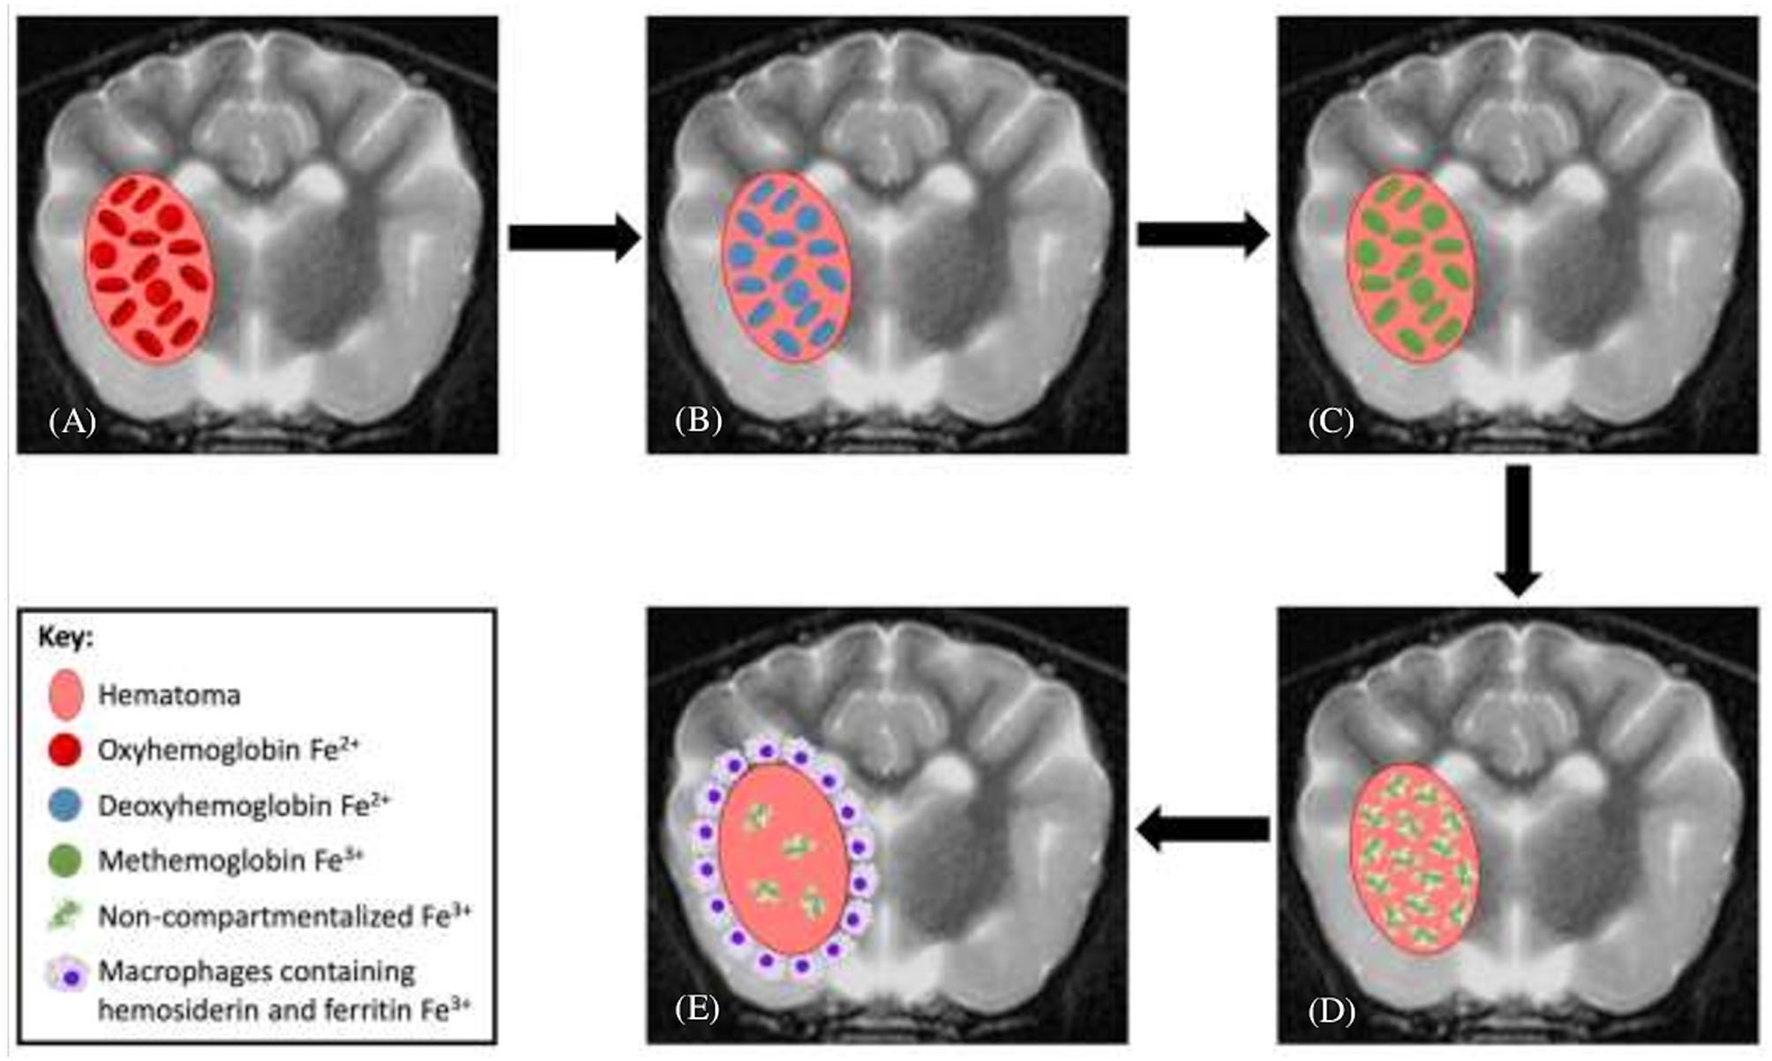

Figure 1

Evolution of intraparenchymal hemorrhage on magnetic resonance imaging. (A) In the earliest stage of acute hematomas, blood is still oxygenated within intact red blood cells (RBCs). (B) Rapid deoxygenation occurs, first at the periphery and then throughout the hematoma, but the RBCs remain intact. (C) As the lesion undergoes oxidation, the peripheral hemoglobin within intact RBCs forms methemoglobin. (D) This oxidation process and conversion to methemoglobin occur throughout the hematoma and subsequently the RBCs lyse. (E) As free methemoglobin is formed, hemosiderin and other iron storage forms are deposited within macrophages in the adjacent brain parenchyma. Eventually, the lesion contains no intact RBCs, and methemoglobin is resorbed or metabolized, leaving only a collapsed cleft lined by hemosiderin and ferritin without any notable central constituents.